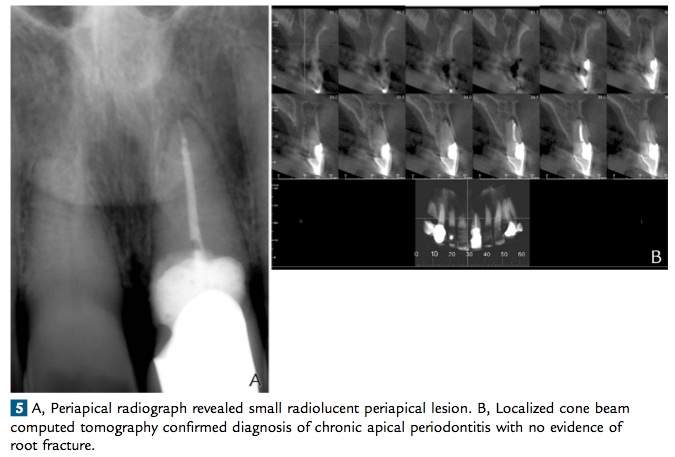

這篇文章是一個case report, 一位78歲的老先生因為在25年前有撞到左上正中門牙, 造成慢性的吸收. 可能是考量年紀的問題所以沒有去植牙(作者群在文章中有提到, 怕牙肉向下萎縮…) 所以他們先做endo, 然後flap op下去補GI modified resin cement, 再做crown. 在六個月後照CT發現facial bone有缺損所以再補一次bone. 後來觀察到30個月結果都是不錯的…